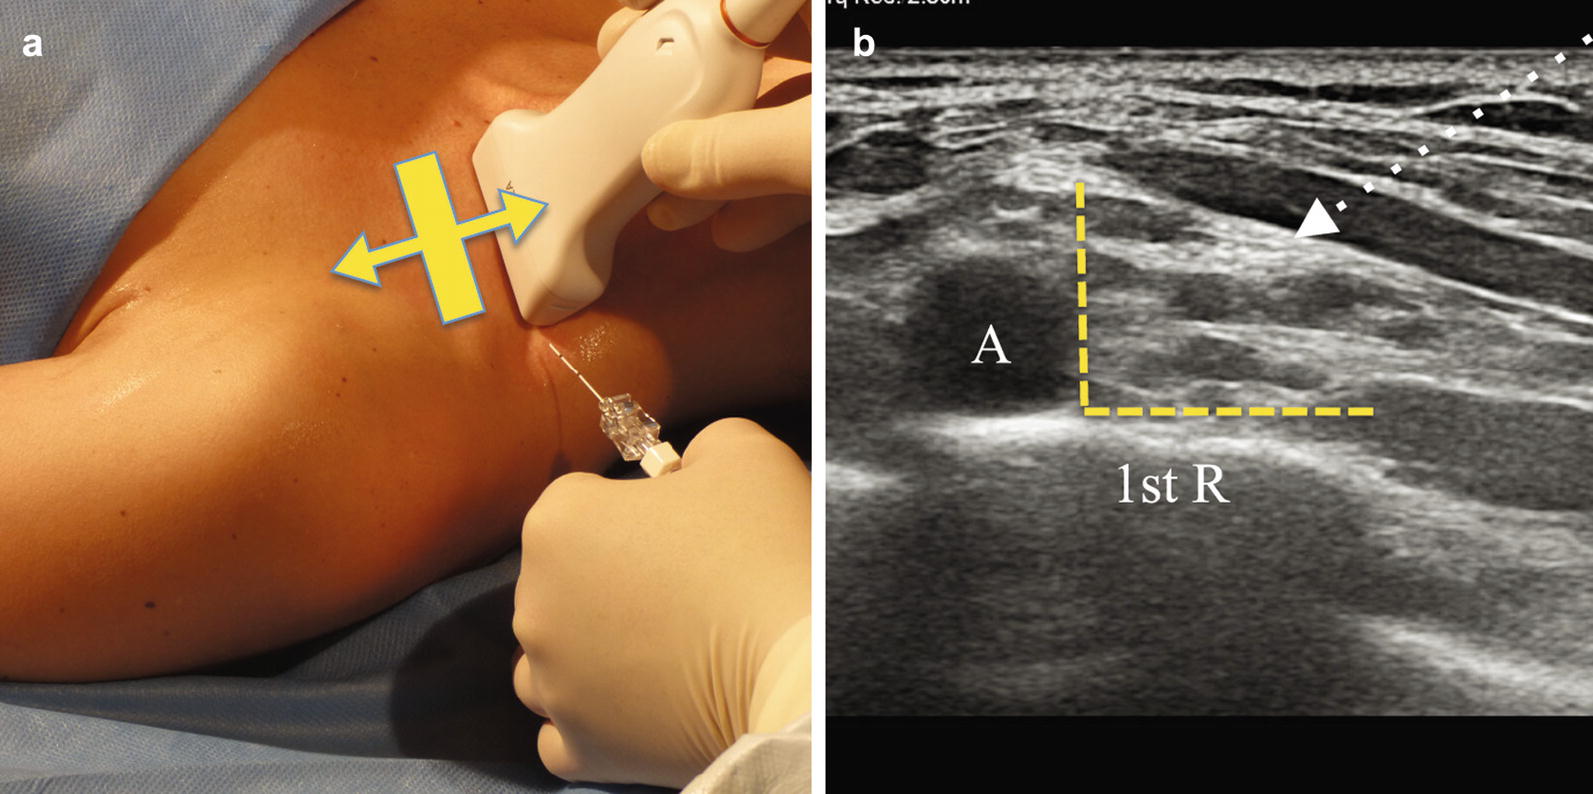

From link.springer.com

USGuided Nerve Blocks Procedure Technique SpringerLink How Long Does A Nerve Block Procedure Take Doctors give therapeutic nerve blocks to treat back and neck pain, and various other types of acute and. The feelings and movement in that part of the body will. a nerve block typically takes less than 10 minutes to administer and up to 30 minutes to take full effect. a nerve block is an injection to treat pain.. How Long Does A Nerve Block Procedure Take.